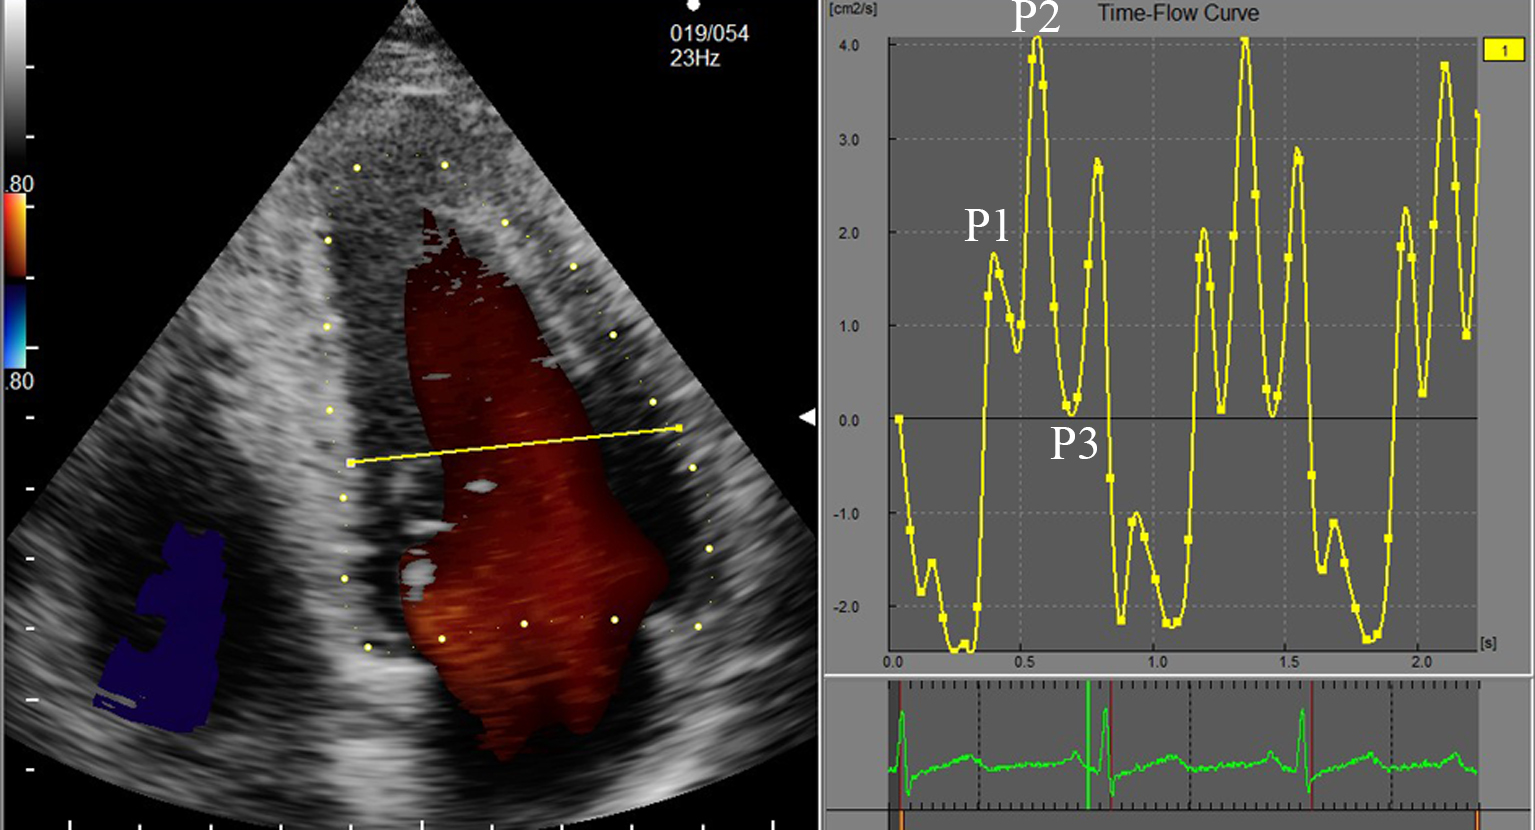

Three cardiac cycles were continuously collected and VFM data was stored on the mobile hard disk for offline analysis. The VFM image data were entered in the DAS-RSI workstation, the analysis interface was entered. The time-flow curve was used to define the time period, and the electrocardiogram (ECG) R-R wave apex was selected as a complete cardiac cycle. Based on the ECG and valve opening and closing conditions, a complete cardiac cycle was divided in three periods: fast filling period (P1), slow filling period (P2), and atrial systolic period (P3) (Fig. 2). The LV diastolic EL-AVE was measured in energy loss mode, and the average EL-AVE value of these three time periods was calculated. The differences in EL-AVE between groups was compared (Fig. 3).

Fig. 2.The LV cardiac cycle time-flow curve. Each point of the curve corresponds to the frame rate of the ECG. The three periods of the diastole: P1—fast filling period, P2—slow filling period, and P3—atrial systolic period.